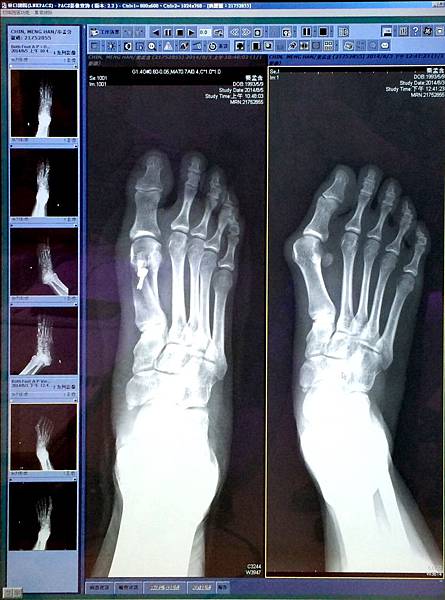

看到術後隔天拍的X光片最開心~~~

因為骨頭變直好多